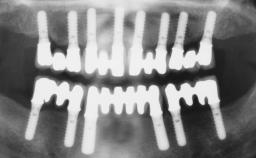

A healthy 31-year-old female patient presented with a failing maxillary left lateral incisor crown. The crown regularly loosened, and the remaining tooth was neither restorable nor rational to treat. The patient had a high smile line, a medium soft tissue biotype with a compromised mesial papilla (shorter than the contralateral one), and a horizontal scar in the buccal soft tissue as a result of past periapical surgery.